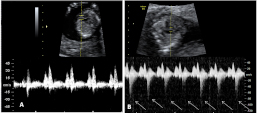

Flujo patológico en el conducto venoso

Doppler en conducto venoso. Registro normal (marcado con la letra A) y registro patológico (letra B), con onda a negativa (flechas).